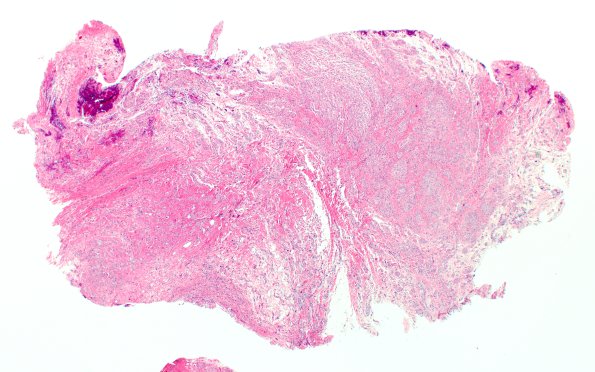

Washington University Experience | PERIPHERAL NEUROPATHY | 19 TRAUMATIC INJURIES | 7A1 Neuroma, brachial (Case 7) H&E 2X

Case 7 History ---- The patient is a 7-month-old girl who suffered a traumatic birth injury that involved shoulder dystocia and a fracture of her right clavicle. She had flaccid paralysis of her right arm at birth with only mild improvement in the strength of her arm after birth. Operative procedure: Brachial plexus exploration and repair with allograft. 7A1-3 Sections of the "brachial plexus injury" show numerous small nerve fascicles (mini-fascicles) in clusters embedded in a fibrous matrix. (H&E)